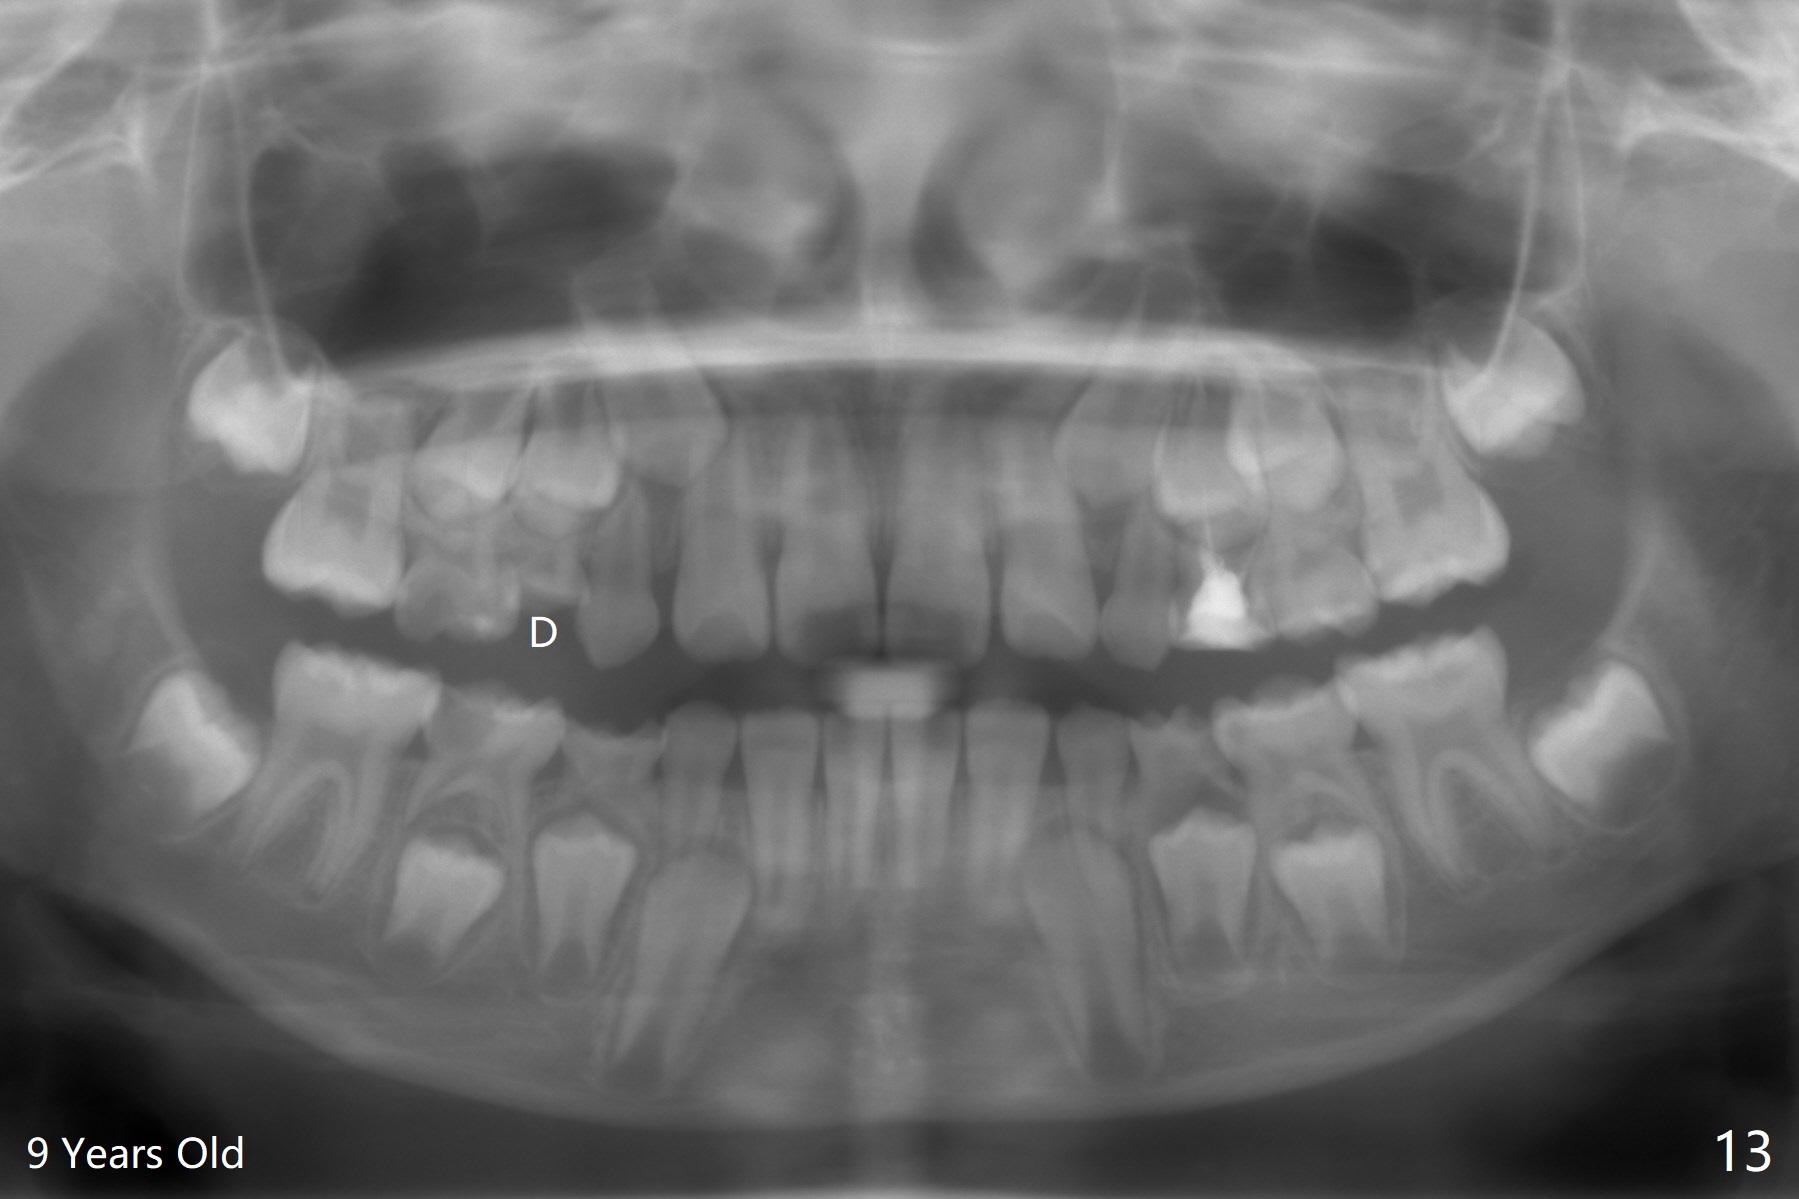

A 14-year-old woman, used to be a dental phobic (Fig.13), agrees with orthodontic treatment. Her mother is concerned about UL1 protrusion (Fig.8,11) and decalcification (Fig.8 *) and UR4 cross bite (Fig.7,10,14). There is mild lip constraint (Fig.1,3), as related to light dental protrusion (Fig.2,4), although the upper dental midline is not deviated (Fig.2). History shows that UR3 erupts before UR D is extracted, which is associated with UR4 cross bite. After arch expansion, consider proximal reduction to reduce anterior overjet if present. In fact that latter is not done; instead Class II is conducted.